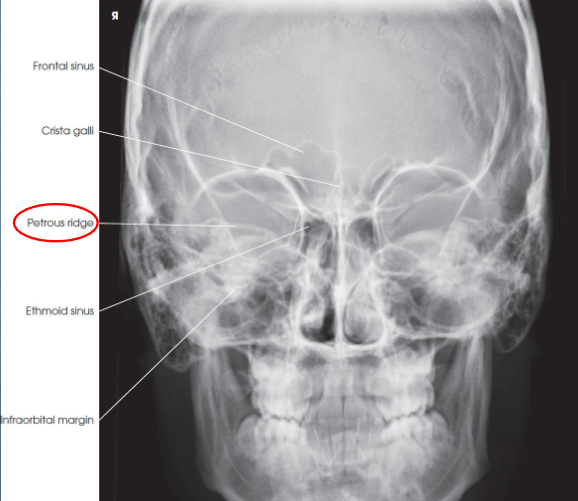

PA axial (Caldwell) facial bones

PA axial (Caldwell) facial bones image criteria

shows:

orbital rims

maxillae

nasal septum

zygomatic bones

anterior nasal spine

petrous ridges in lower third of orbits (caused be 15 degree caudal angle)

entire orbits and facial bones

no rotation or tilt:

equal distances from lateral borders of skull and lateral borders of orbits

MSP of head alligned with long axis of collimated field

symmetric petrous ridges